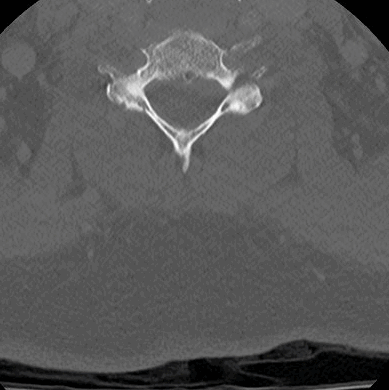

CT Thoracic Spine Contrast- Bone window (axial)